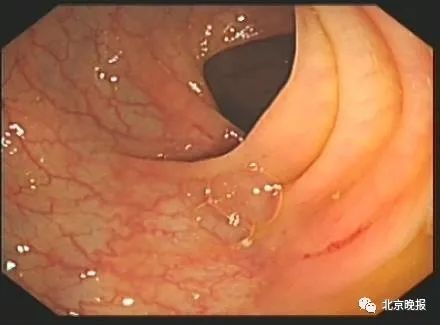

正常结肠黏膜